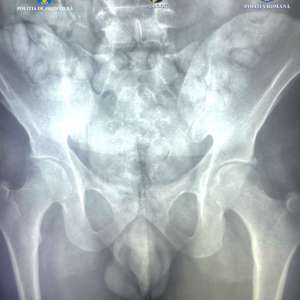

During a body scan using an X-ray scanner provided by the Border Police, several unusual formations were observed inside the suspect's abdomen, which did not correspond to human anatomy. Consequently, the suspect was taken to a medical facility, where, during hospitalization, he expelled 62 capsules containing approximately 350 grams of powdered substance (currently undergoing forensic analysis).